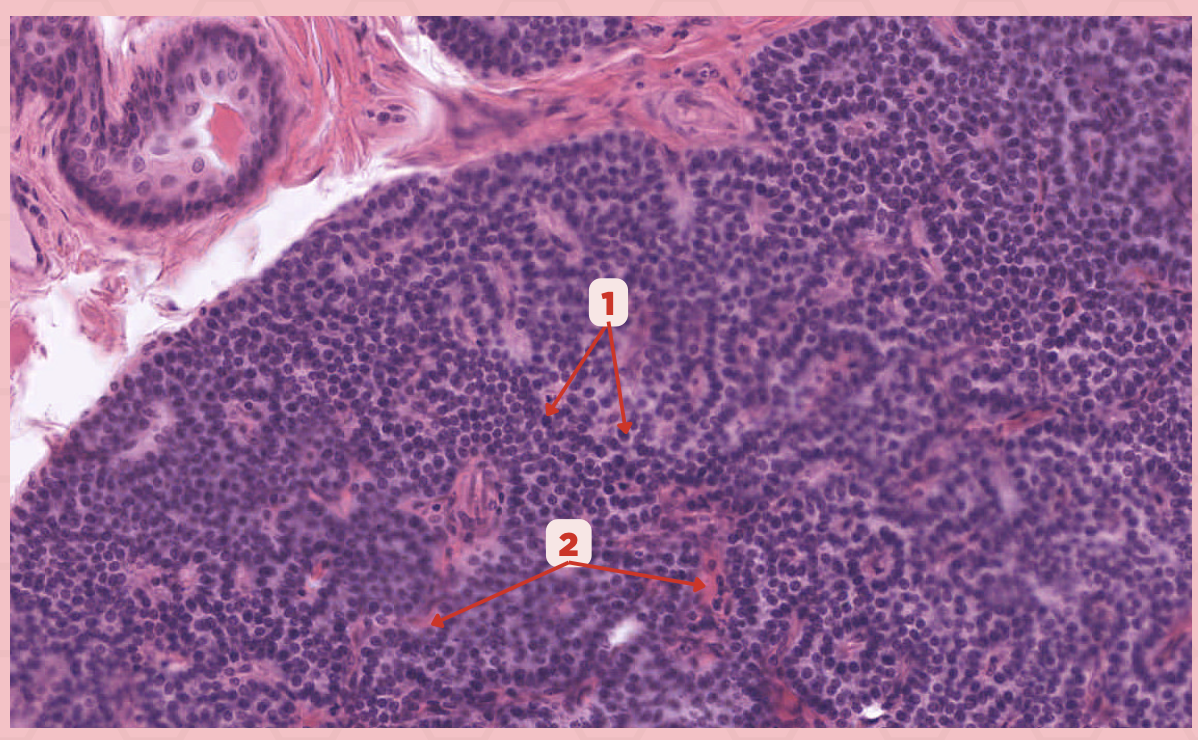

Parathyroid

Identify the specimen.

Chief Cells

Identify the structure labeled as 1. This comprise the majority of cells in the parathyroid gland.

Septa

Identify the structure labeled as 2.

Parathyroid hormones

What hormones are synthesized and secreted by the cell in Pointer #1?

Parathyroid

Identify the specimen.

Chief Cells

Identify the specimen labeled as 1.

Oxyphil Cells

Identify the specimen labeled as 2.

Adipocytes

Identify the specimen labeled as 3.

Capillaries

Identify the specimen labeled as 4.

Newborns

Pointer #2 is hardly present in the parathyroid glands of _____.